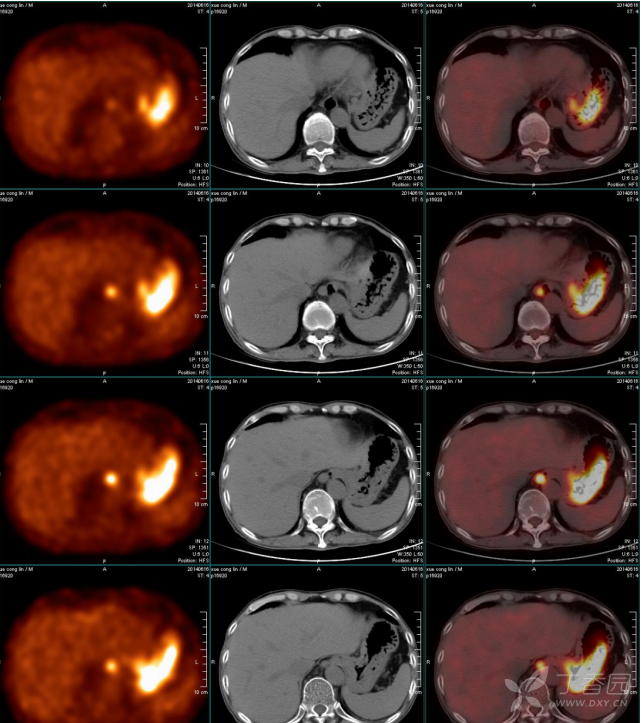

pet-ct:淋巴瘤? - 影像医学和核医学讨论版 -丁香园论坛

图片尺寸672x753